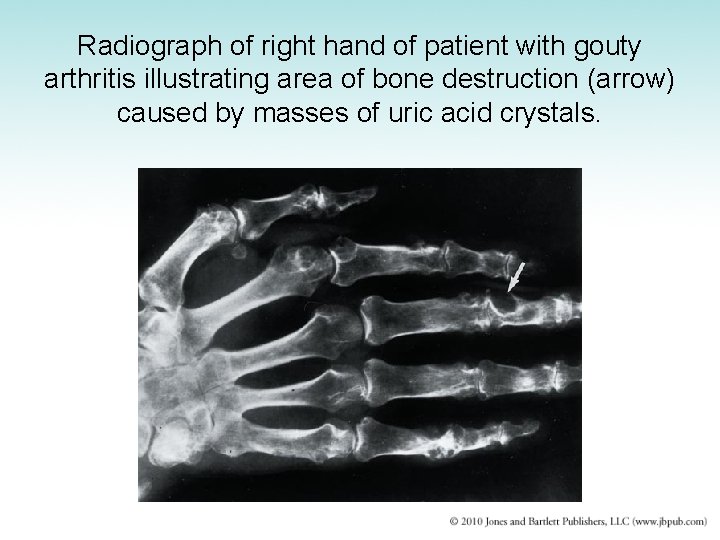

Gout • Disorder of purine metabolism – Uric acid: an insoluble end-product of purine metabolism – Acute episodes caused by precipitation of uric acid crystals in joint fluid – Uric acid stones also may form within kidney and lower urinary tract • Urate nephropathy: urate deposits plug tubules and damage kidneys – Treatment: diet and drugs that lower uric acid

Radiograph of right hand of patient with gouty arthritis illustrating area of bone destruction (arrow) caused by masses of uric acid crystals.